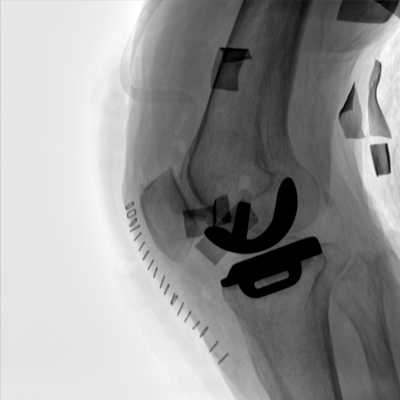

大尺寸動態(tài)平板探測器,高DQE、低噪聲、圖像清晰。采用多分辨率圖像增強處理技術(shù),不同部位不同圖像處理算法,滿足客戶多樣化的需求。

圖形化操控界面設(shè)計:設(shè)有多種人體特征攝影參數(shù),操作簡便。雙向紅光十字定位系統(tǒng):實現(xiàn)無射線下的高效定位。信息共享:遵循DICOM3.0格式接口,可無縫對接云PACS系統(tǒng)。